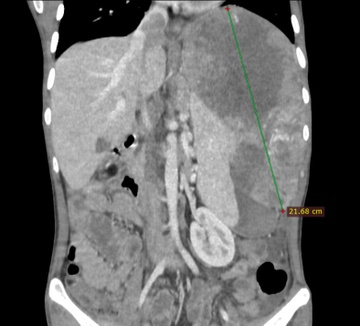

Hình ảnh khối u gan kích thước lớn của bệnh nhân 26 tuổi. Ảnh: BSCC.

Kể lại với Tri Thức - Znews, bác sĩ chuyên khoa II Nguyễn Trường Giang, cho biết tiếp nhận bệnh nhân trong tình trạng ốm yếu, chỉ nặng có 40 kg vì đau không ăn uống được và nhiều ngày dùng thuốc không rõ nguồn gốc, khối u gan đường kính hơn 20 cm, xâm lấn tĩnh mạch chủ dưới, đã vỡ gây chảy máu ồ ạt.